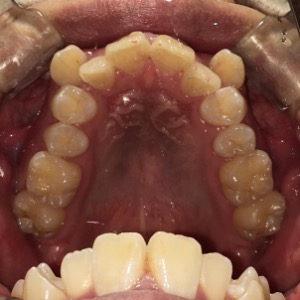

症例

before

患者さんの年齢 30代 男性 症状 ガタガタを治したい 治療内容 ワイヤー矯正治療 費用 88万(税抜) 治療期間・回数 治療期間2年半、通院回数20回 メリット 口元が綺麗 デメリット・リスク 期間がかかることがある 患者さまの声 見た目が良くなった - 矯正治療